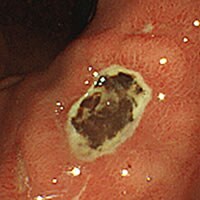

胃潰瘍瘢痕(胃潰瘍のあと)

胃の調子がずっと悪いといって胃カメラをやったところ、胃潰瘍の痕(あと)がたくさんあることがわかりました。

本人気が付かないところで、実は胃潰瘍に何回かなっていたんですね。その後胃薬飲んだら調子がいいとのことです。